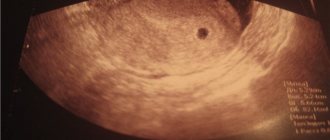

Читайте также:  УЗИ на 5 неделе беременности: как выглядит, для чего делают, нормальные показатели Запишитесь на диагностику или консультацию уже сегодня! Записаться можно по телефону: +7 (812) 901-03-03 Или оставьте заявку ФИО Номер телефона Нажимая кнопку «Записаться на прием» я соглашаюсь с условиями Политики в области обработки персональных данных УЗИ на 5 акушерской неделе беременности Для выполнения УЗИ-скрининга во время беременности установлены стандартные сроки. Для первого триместра это 10-13 недель, для второго – 20-24, для третьего – 32-34 недели. Но в ряде случаев ультразвуковая диагностика может производиться не только в эти периоды, но и ранее. Достаточно часто женщинам назначают УЗИ на 5 неделе беременности. Это тот период, когда эмбрион уже может визуализироваться, а его сердце начинает биться. Для чего делают УЗИ на 5 неделе беременности? УЗИ на 5 акушерской неделе беременности проводится с целью: Подтвердить беременность. На сроке в 5 недель тест на беременность уже должен показывать две полоски, хотя редкие ошибки случаются. Чтобы на 100% подтвердить беременность, можно провести ультразвуковой скрининг. Подтвердить правильное прикрепление плодного яйца. Закрепиться оно должно в матке, в противном случае (например, когда плодное яйцо закрепилось в маточной трубе) диагностируется внематочная беременность. Оценить жизнедеятельность эмбриона в плодном яйце. Выявить многоплодную беременность. Опровергнуть вероятность того, что повышенный уровень ХГЧ, на который среагировал тест на беременность, не является следствием патологии женской репродуктивной системы. Выявить угрозы невынашивания беременности. Как правило, на таком раннем сроке УЗИ назначают тем женщинам, которые:Ранее переносили кесарево сечение. В этом случае нужно посмотреть, как прикрепился хорион (который впоследствии станет плацентой). Близкое прикрепление к рубцу на матке или прикрепление непосредственно к рубцу может стать серьёзной угрозой невынашивания плода. Ранее переносили выкидыши. Ранее имели замершую или внематочную беременности. Забеременели с помощью процедуры ЭКО. Что происходит с плодом на пятой неделе? На протяжении первых четырёх недель беременности плод развивался с невероятной скоростью. На пятой неделе у него уже начинает биться сердце, развивается сердечно-сосудистая и нервная системы. Также происходит формирование позвоночника, спинного мозга, а головной мозг плода теперь состоит их двух долей. Плод к пятой неделе приобретает грушевидную форму и в длину достигает примерно 4 мм. Такие размеры уже могут визуализироваться при УЗИ сканировании. Округлая часть эмбриона в будущем преобразуется в голову малыша, а острая – в позвоночник. Также на пятой неделе происходит закладка внутренних органов плода: печени, поджелудочной железы, гортани, трахеи. Как подготовиться к УЗИ? Такая процедура, как УЗИ на 5 неделе беременности, требует небольшой подготовки. За 2-3 дня до обследования нужно исключить из рациона продукты, приводящие к чрезмерному газообразованию в кишечнике. Также перед УЗИ нужно опорожнить мочевой пузырь. Как делают УЗИ на пятой неделе беременности? На таком раннем сроке, как 5 недель, УЗИ делают трансвагинально, вводя специальный датчик внутрь влагалища беременной женщины. Предварительно на датчик надевается специальный медицинский презерватив. Трансвагинальное УЗИ – процедура безболезненная, но некоторый дискомфорт беременной женщине она доставить может. Не рекомендуется проводить подобную диагностическую процедуру, если у женщины наблюдаются кровянистые выделения либо она жалуется на боли в животе. Что покажет УЗИ на 5 неделе беременности? Ультразвук на пятой неделе беременности покажет плодное яйцо с эмбрионом внутри (при нормальном, стандартном течении беременности). Также по результатам сканирования можно будет судить о прикреплении хориона, расположении плодного яйца в полости матки. Если плодное яйцо не дошло до матки и закрепилось, например, в маточной трубе, УЗИ покажет это, и женщине будет поставлен диагноз внематочная беременность. УЗИ на 5-й неделе покажет сердце малыша, позволит оценить частоту его биения. Уже на таком малом сроке можно будет заподозрить возможные патологии сердца плода, хотя однозначный вывод о наличии/отсутствии порока сердца сделать трудно. УЗИ покажет, насколько активно развивается нервная трубка плода, которая впоследствии станет костным мозгом ребёнка. Движения эмбриона Для оценки жизнеспособности плода и его самочувствия в утробе матери оценивается частота его сердечных сокращений. Нормы и расшифровка Выделяют несколько основных параметров развития плода, которые учитываются при расшифровке результатов ультразвука: размер эмбриона – нормативное значение около 4 мм; размер желточного мешка – нормативное значение 4-5 мм; размер плодного яйца – по норме он должен составлять примерно 1 см; ЧСС – норма от 70 до 100 уд/мин. Также по УЗИ можно оценить вес эмбриона – он должен составлять примерно 4 г. Результаты УЗИ – это не единственная информация, которая должна приниматься во внимание при постановке того или иного диагноза. Важно также оценить анализы крови, мочи и результаты других дополнительных исследований. Если на УЗИ эмбрион не видно Если УЗИ на 5-й акушерской неделе беременности покажет, что есть плодное яйцо, но эмбриона в нём не видно, это ещё не повод для серьезного беспокойства. Вероятно, возможности аппарата не настолько велики, чтобы разглядеть эмбрион на столь раннем сроке. Для подтверждения беременности можно пройти ультразвук чуть позже – в 6-7 недель. Возможен и более печальный прогноз. Отсутствие визуализации эмбриона может говорить о замершей беременности либо о анэмбрионии (то есть зарождение эмбриона не произошло либо он погиб сразу после зарождения). Лечащий врач в таких случаях должен разобраться в причинах произошедшей гибели эмбриона и назначить женщине определённые обследования.

Когда видно плодное яйцо на УЗИ?

В первую неделю-две после момента оплодотворения ультразвуковое обследование не может дать объективные результаты. Медики рекомендуют проходить данную процедуру только на 27-30 день после

предполагаемого момента зачатия ребенка. В редких случаях очертания и размеры можно идентифицировать уже на 21 день.

Опытные врачи могут детектировать сам факт наличия беременности на самых ранних этапах благодаря характерному утолщению стенок матки.